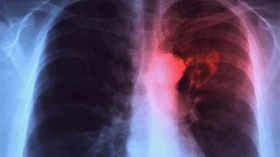

إصابة 5 تلاميذ بداء “السل” في ثانوية بسطيف